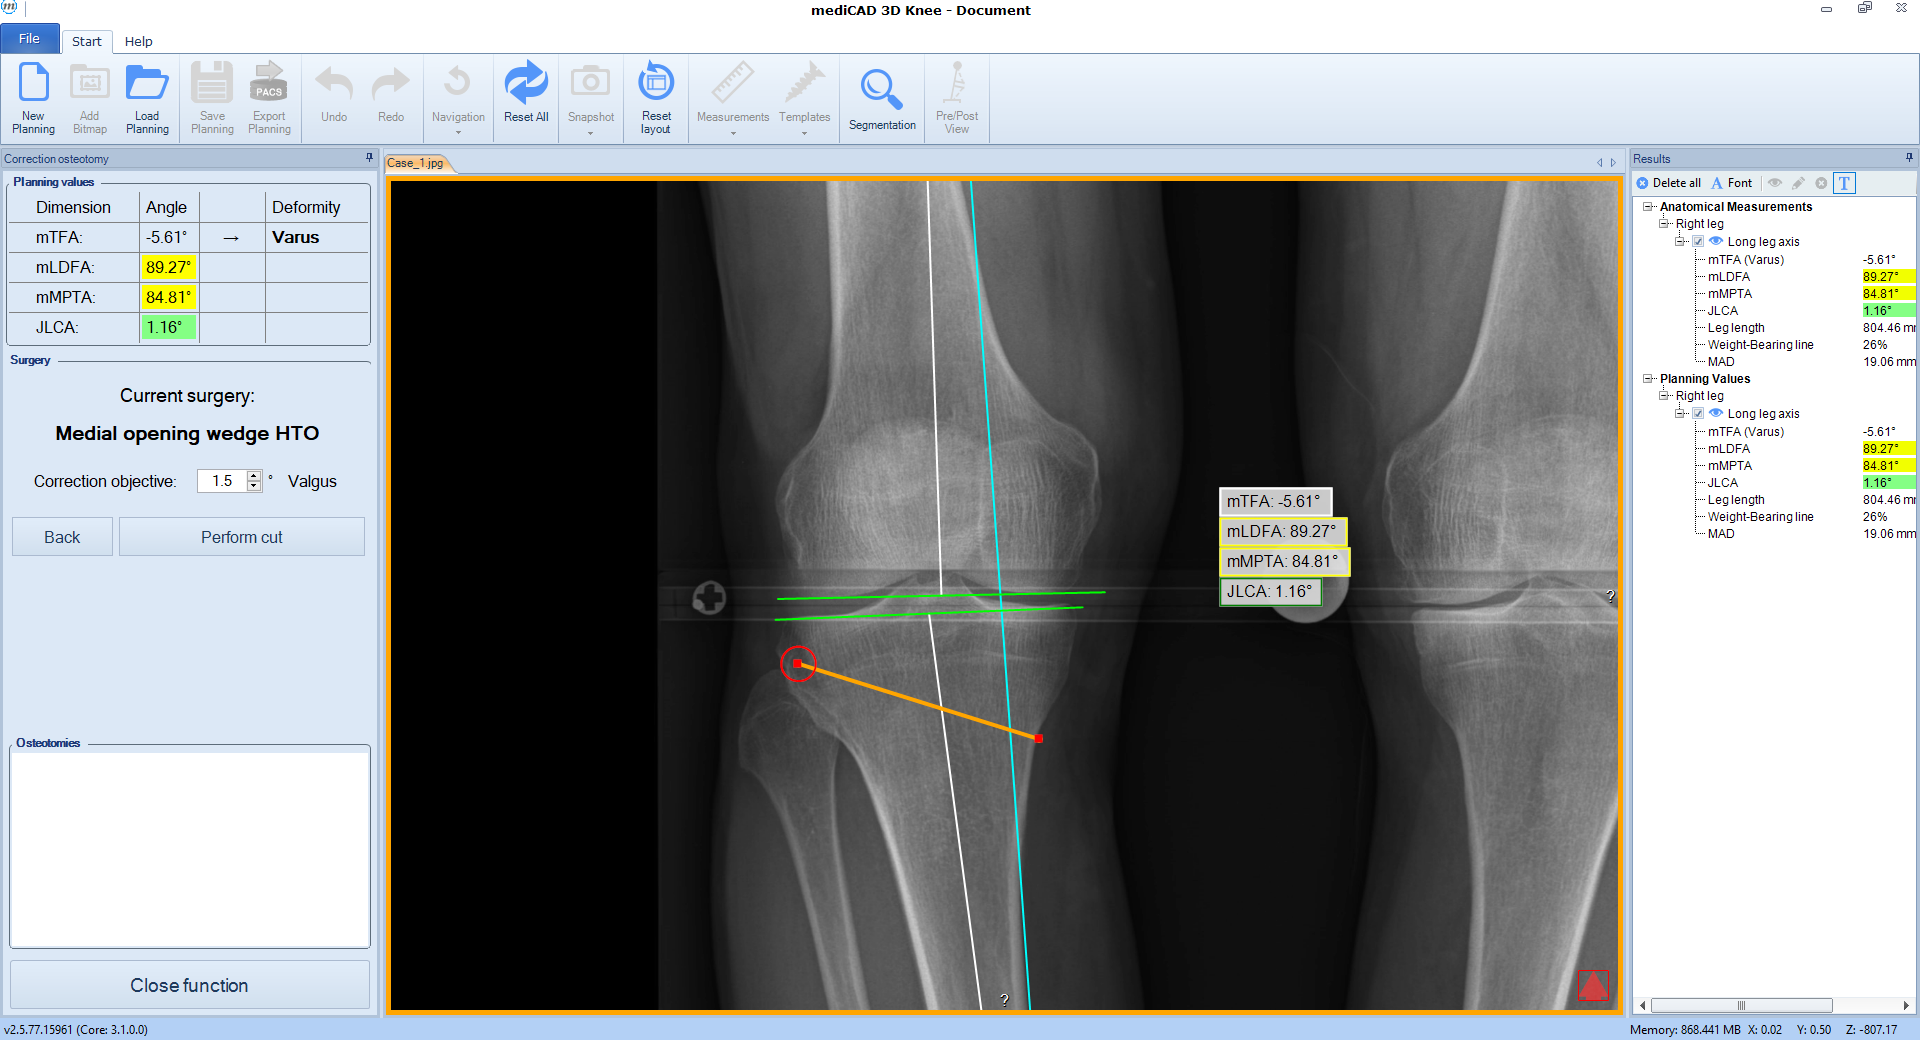

Once the procedure is selected, the software automatically places the cutting line and hinge point for the chosen osteotomy adapted to the individual anatomical condition (Fig 3).

Case 1

(Case provided by Stefan Schröter)

A 33-year-old woman complained of pain in the lateral compartment after a normal working day. Sports activities were no longer possible. Free range of motion (ROM: 0/0/150°), ligaments in sagittal, and coronal planes were stable. There was no effusion. The patient had valgus deformity which was corrected with a distal femoral osteotomy.

A 52-year-old man with a posttraumatic deformity 2 years after tibial plateau fracture AO/OTA 41C3.3e, PL, PM complained of pain after a normal working day. The patient was a heavy smoker. Activities like sports or hiking were discontinued. Surprisingly ligaments in the coronal and sagittal planes were stable. There was no effusion. Pain was localized in the medial compartment. The range of motion was limited to 0/0/130°. The deformity was corrected with a high tibial osteotomy.